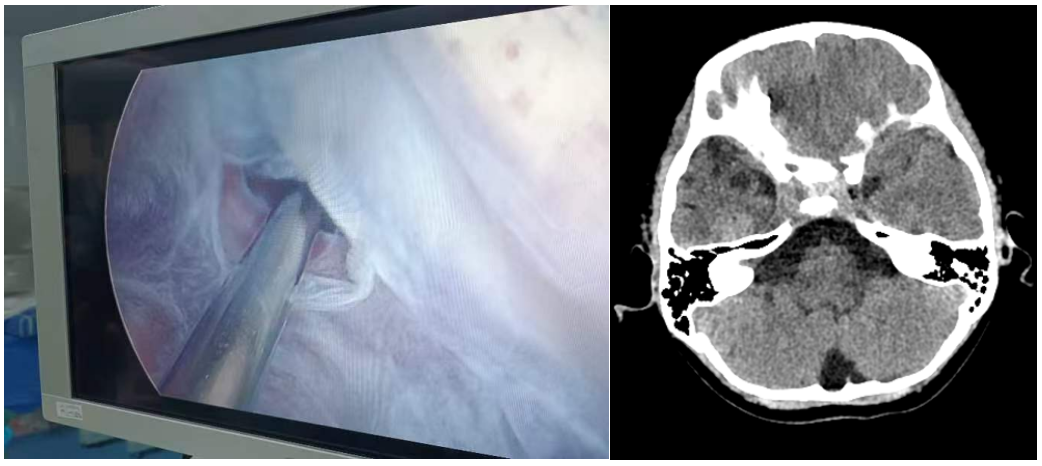

1.小骨窗显微手术:是治疗儿童脑型肺吸虫病的有效方法,具有缩短手术时间,显微镜下顺利寻找病灶边界,减少对周围正常脑组织的牵拉。手术创伤小、恢复周期短,做到对脑组织及周围神经损伤最小。

3.颅内肿瘤